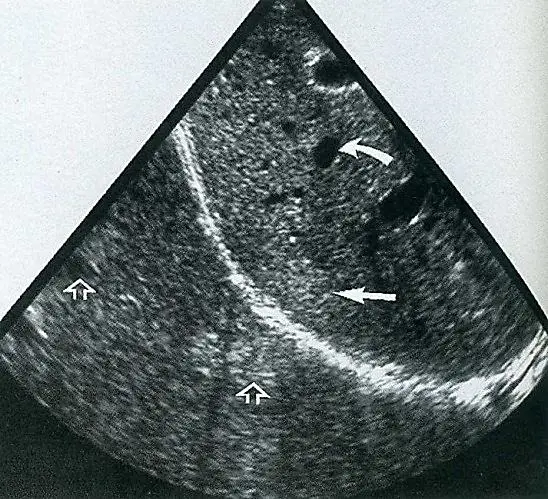

下圖為超音波掃描影像,影像中空心箭頭處發生了何種假影?

觀察本題提供的超音波(B-mode)影像,可以辨識出以下重要結構與特徵:

- 明亮的弧形高回音線(亮線):位於影像中央偏左下方,這是典型的**橫膈膜(Diaphragm)**影像,在超音波中扮演著一個「強反射面(Strong reflector)」。

- 弧形亮線以上的區域(較淺層):為肝臟實質(Liver parenchyma),其中實心彎曲箭頭指著一個圓形的無回音區(anechoic area),可能為肝囊腫(hepatic cyst)或血管結構。實心平直箭頭則指著肝臟的實質組織。

- 弧形亮線以下的區域(較深層):原本橫膈膜下方應為充滿空氣的肺部,正常情況下超音波無法穿透空氣,應呈現全反射或是雜亂無章的假影。然而,影像中卻出現了與亮線上層完全對稱的「肝臟實質影像」,且**空心箭頭(題目所指)**正指著這塊位於橫膈膜深處、與真實肝臟特徵相同的異常影像區域,甚至連上方的圓形無回音